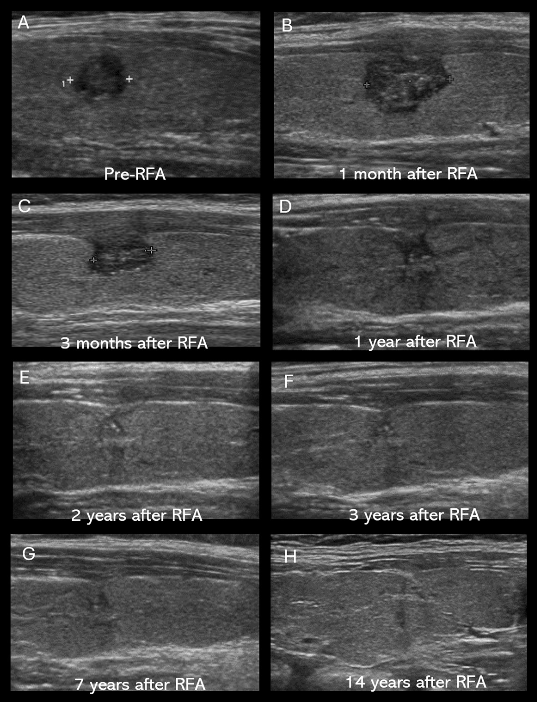

The study tracked 65 patients who received RFA between May 2008 and December 2013, analyzing a total of 71 thyroid microcarcinomas over a follow-up period of more than 10 years.

The results showed that all tumors completely disappeared within two years. There were no cases of local recurrence, lymph node metastasis, distant metastasis or thyroid cancer-related deaths. Reported side effects included one case of mild hypothyroidism requiring medication, accounting for 1.4 percent, two cases of bleeding and one case of second-degree burns.